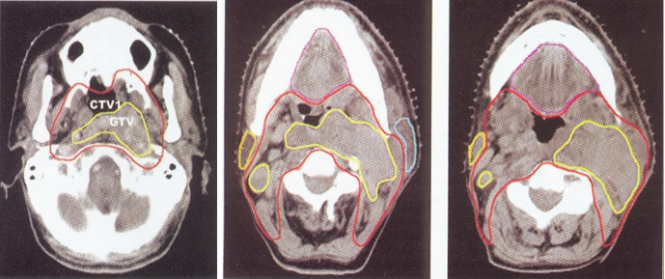

靶区勾画:

GTV 原发肿瘤和可能的淋巴结转移

CTV 包括GTV和必须消除的亚临床病灶

PTV 包括CTV同时考虑器官运动和摆位误差

危及器官勾画:

通常需要勾画的危及器官有:脑干、晶体、视神经、腮腺、脊髓、肺、心脏、肝、肾、小肠、膀胱、直肠等,因为这些组织和器官严重受损将会给病人带来严重后果。